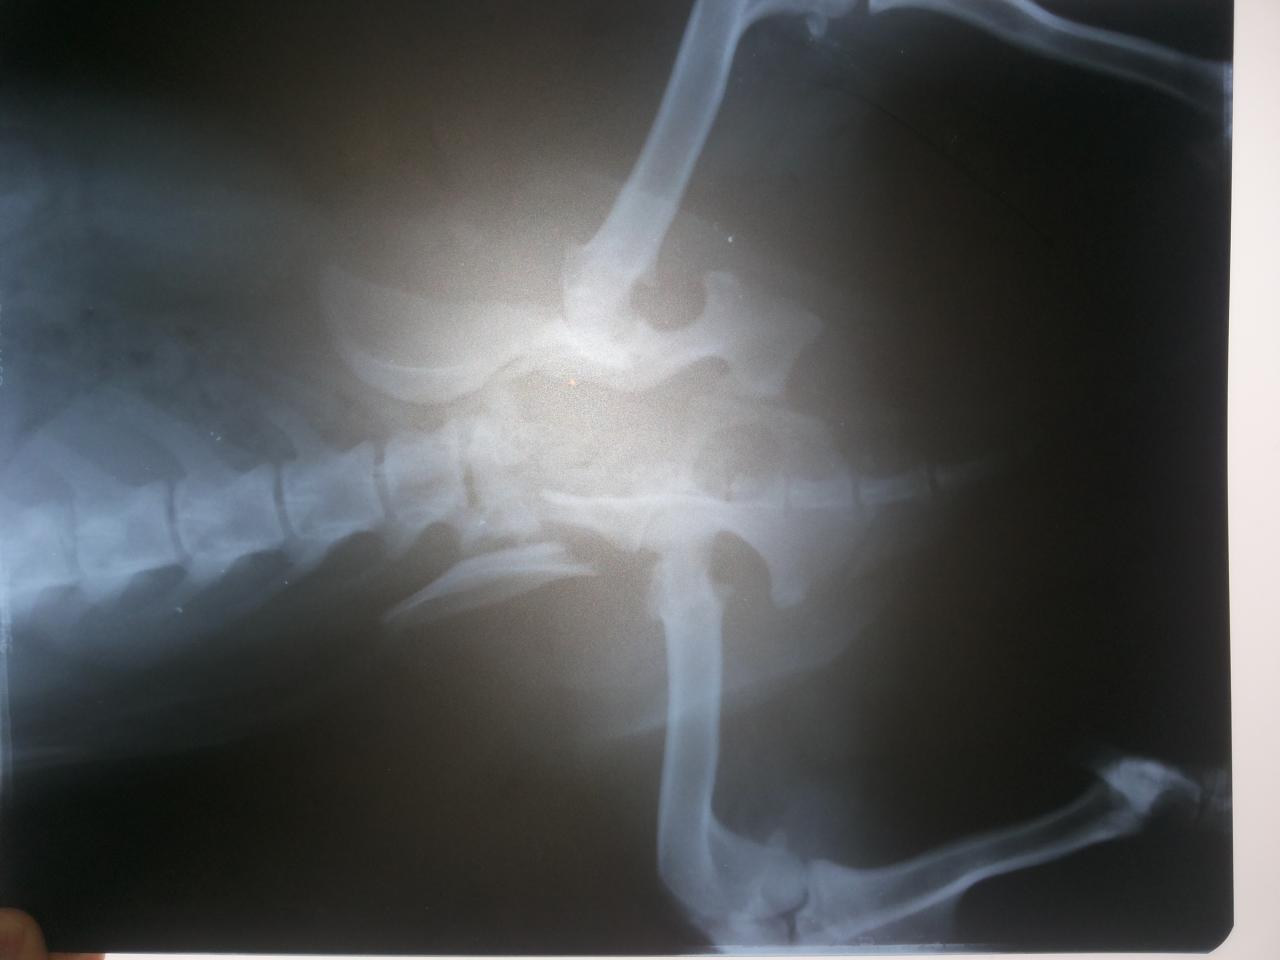

По результатам Рентгена всё очень плохо: 2-й перелом таза.